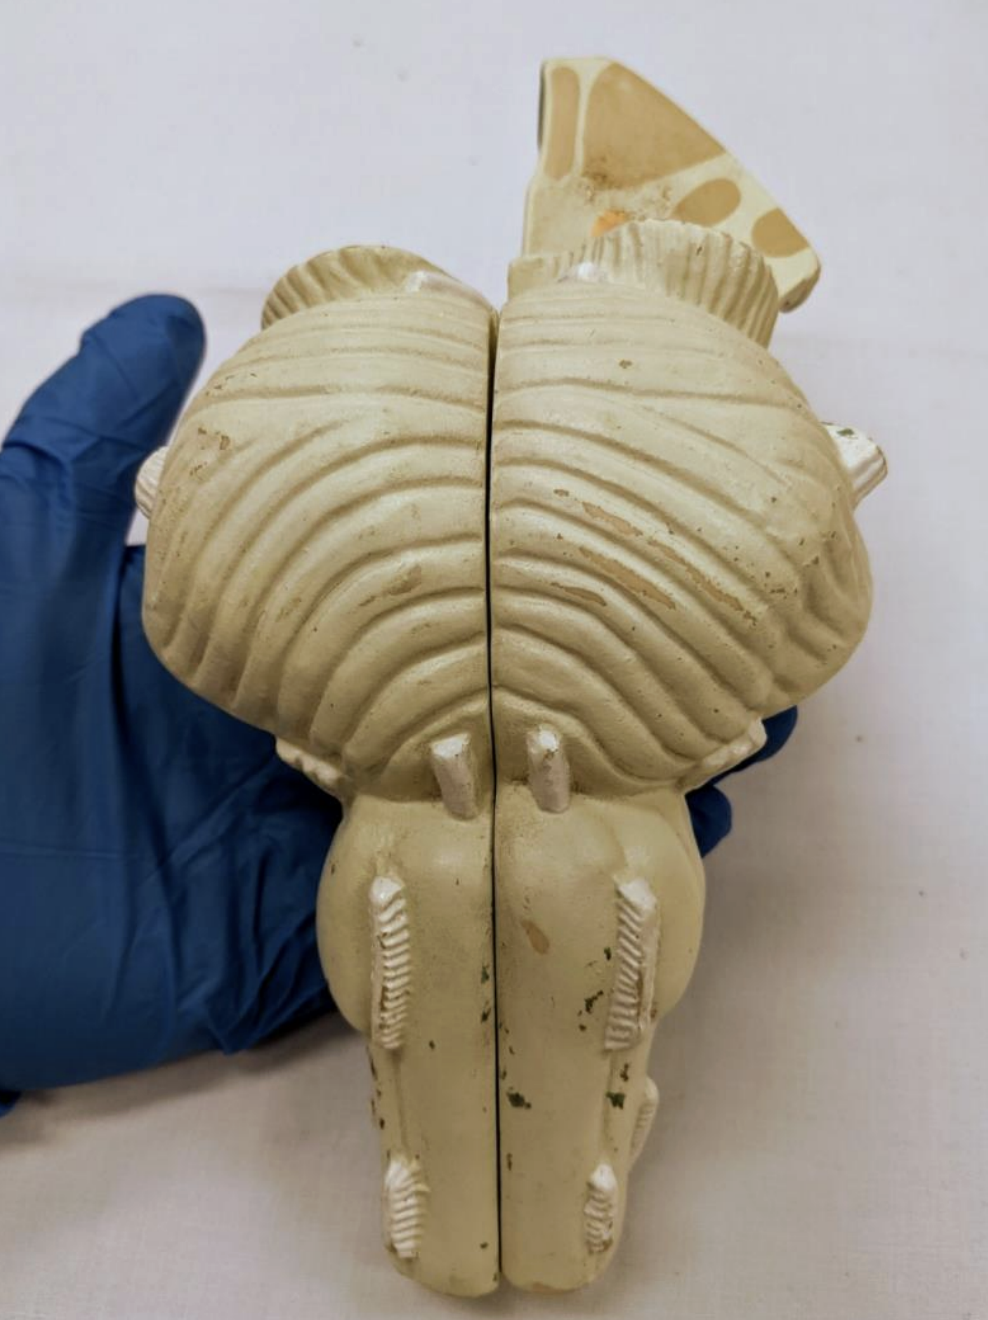

Cerebellum

Anterior lobe of cerebellum

Horizontal fissure

Posterior lobe of cerebellum

Cerebellar tonsils

Posterolateral fissure

Superior medullary velum

Arbor vitae

Folia